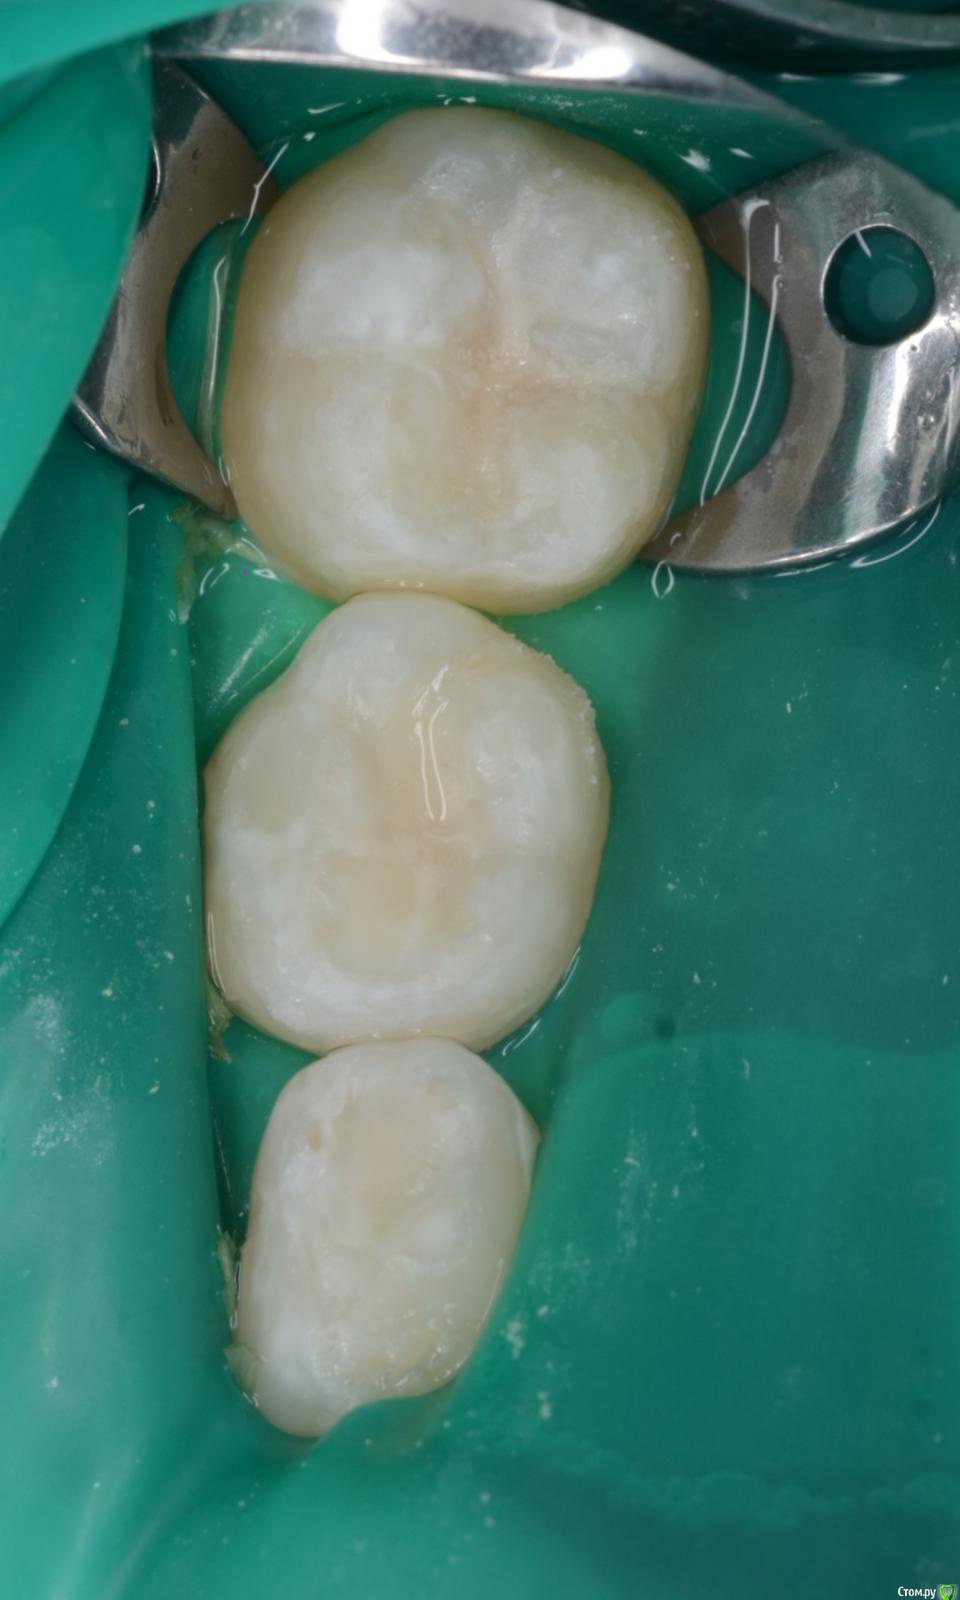

CRAZYDUCK Опубликовано 30 мая, 2018 Автор Поделиться Опубликовано 30 мая, 2018 Про обратимый пульпит .( ампутацию) Лечение методом витальной АМПУТАЦИИ. Даше в июле 6 лет . Познакомились мы полтора года назад , но сотрудничать не получилось , направлены для лечения в условиях общего обезболивания ( наркоз ) к ☺ @toothfairymila После лечения в условиях наркоза дети легче идут на контакт . Ребёнка не узнать - если до лечения в наркозе Даша даже в кресло садилась со слезами , то после - милые подарки , осторожно , но готова сотрудничать . Даша внимательно смотрит на моих ассистентов , взгляд изучающий ( можно этому человеку доверять или нет ). Маме Даши огромное спасибо - очень ответственно относится к регулярным осмотрам . Выявили скрытые кариозные полости и Даша доверилась лечиться в обычных условиях ( без наркоза ). 6.4 - обратимый пульпит , изначально было обширное разрушение , восстановлено пломбой в наркозе , поэтому лепить там пломбу ещё больше нет смысла. После ампутации -спонтанный гемостаз ( сравните с предыдущим случаем). Промываем ХГ 2% , мта на устья , IRM , коронка. 6.5 - обширная реставрация окклюзионно и начался кариес на медиальной контактной поверхности . Зуб должен меняться примерно в 10 лет ( 9-11 лет средний срок), то есть хочется , чтобы он постоял ещё года четыре , поэтому покрываем коронкой . Ждём Дашу на осмотр через 3-4 месяца.П.С. На заметку молодым коллегам - На снимке обвела зелёным нерентгенконтрастную реставрацию на зубе 6.3 , похоже на кариес , но это очень хорошая реставрация ! 1 Ссылка на комментарий

CRAZYDUCK Опубликовано 30 мая, 2018 Автор Поделиться Опубликовано 30 мая, 2018 Продолжительность лечения двух зубов меньше часа . 4 Ссылка на комментарий

CRAZYDUCK Опубликовано 30 мая, 2018 Автор Поделиться Опубликовано 30 мая, 2018 Мне так нравятся эти голубые платки ( три смайлика с сердечками в глазах ) 1 Ссылка на комментарий